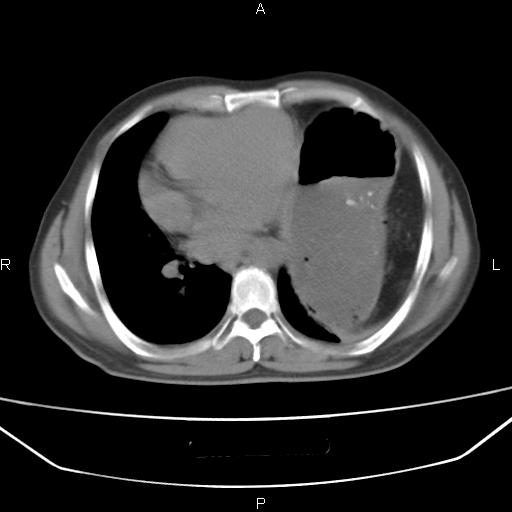

患者,男。50岁。近几日有咳嗽症状,无其他不适,既往病史无,考虑膈疝。请前辈们看看指导指导。

膈膨升,左下肺通气不良,膈肌好像还完整。

考虑左侧膈疝。

左侧膈疝。

符合隔膨升,膈肌较完整。